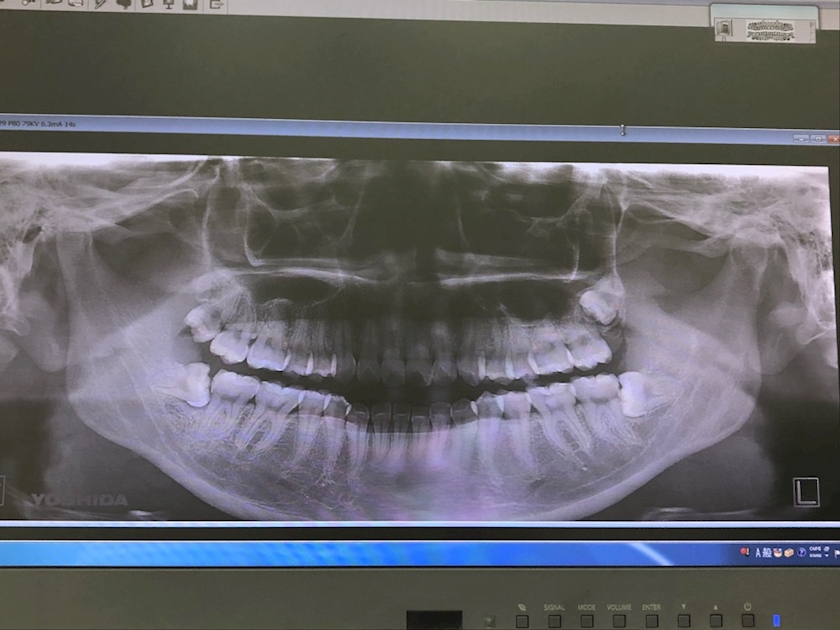

下の両奥歯見てください!

真横に生えてるwwwwwwww

もうこれが原因でしかないです😫💦